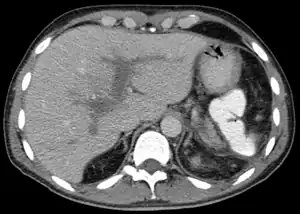

| Portal vein thrombosis seen with computed tomography. | |

Computed tomography scan showing portal vein thrombosis (with cavernous change of portal vein )

The diagnosis of portal vein thrombosis is usually made with imaging confirming a clot in the portal vein; ultrasound is the least invasive method and the addition of Doppler technique shows a filling defect in blood flow. PVT may be classified as either occlusive or nonocclusive based on evidence of blood flow around the clot.[5] An alternative characterization based on site can be made: Type 1 is limited to the main portal vein, Type 2 involves only a portal vein branch (2a, or 2b if both branches are affected), and Type 3 if clot is found throughout both areas.[8] Determination of condition severity may be derived via computed tomography (CT) with contrast, magnetic resonance imaging (MRI), or MR angiography (MRA). Those with chronic PVT may undergo upper endoscopy (esophagogastroduodenoscopy, EGD) to evaluate the presence of concurrent dilated veins (varices) in the stomach or esophagus.[3] Other than perhaps slightly elevated transaminases, laboratory tests to evaluate liver function are typically normal.[1] D-dimer levels in the blood may be elevated as a result of fibrin breakdown.